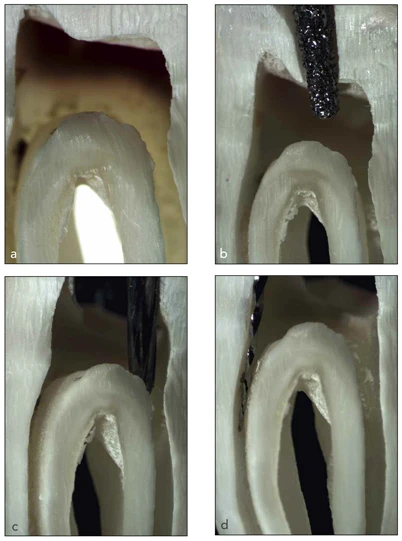

Tiếp đó, chỉnh sửa toàn bộ đường viền ngoài để có một lối vào hơi phân kỳ. Tại thời điểm này, chúng ta phải nhìn trực tiếp được tất cả các lỗ ống tủy và đặt cây thăm dò vào lỗ ống tủy mà không tiếp xúc quá mức với các thành. Đối với răng hàm lớn hàm dưới, bắt đầu mở tủy từ hố trung tâm và góc mũi khoan hơi hướng về phía xa. Buồng tủy được định hình và lấy hết trần như đã giải thích ở trên (Hình 16-7).

Hình 16-7 Bước quan trọng trong quá trình mở tủy trên răng hàm lớn hàm dưới thực hiện trên 1 răng đã được nhổ nhìn trên kính hiển vi. (a) Buồng tủy từ phía bên. (b) Thâm nhập vào ngà với mũi khoan kim cương có phần đầu có tác dung cắt. (c) Chỉnh sửa lối vào với mũi khoan EndoZ có phần đầu không có tác dụng cắt (Dentsply). (d) Loại bỏ các tam giác ngà, ở đây là bằng một dụng cụ quay niken-titanium với phần bên có tác dụng cắt dùng với động tác chải.